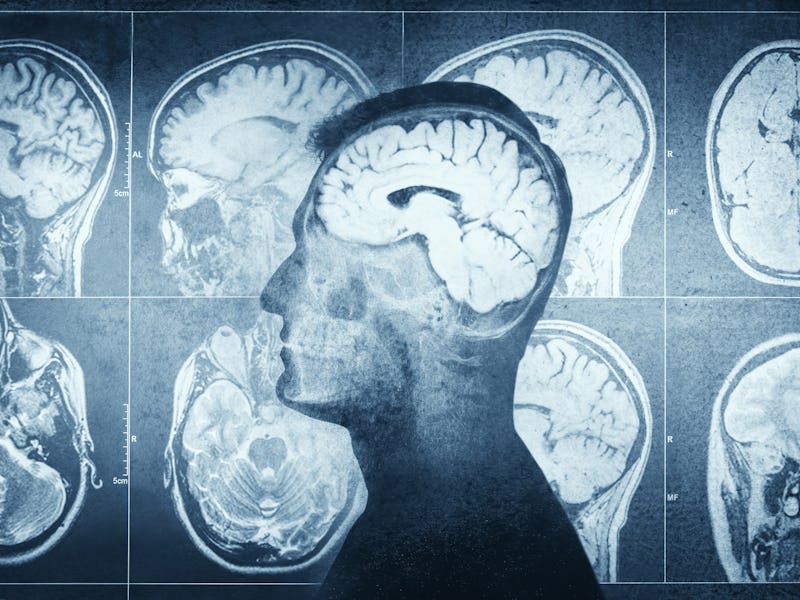

In a study published this month in the Journal of Alzheimer’s Disease, a group of Canadian researchers compared brain imaging between obese people and people with Alzheimer’s disease. They found both groups shared similar patterns in brain volume loss, particularly gray matter, which are regions throughout the brain where neurons are concentrated.

To do that, the researchers tapped into the UK Biobank, a large-scale database containing biomedical information on a half million British individuals, and the Alzheimer’s Disease Neuroimaging Initiative (ADNI) launched in 2003. From both, Morys and his colleagues took brain images called structural MRIs (which provide information on the shape, size, and integrity of the brain and its structures) from a sample of over 1,300 individuals. These were used to create brain maps to identify the location of structural brain changes. For the obesity brain maps, MRIs of obese people were assembled by comparing them against brain scans of lean individuals (both sourced from the UK Biobank). For the Alzheimer’s disease brain maps, the researchers used a similar approach but compared MRIs of afflicted patients against a neurologically healthy control group (both from ADNI). Whether an individual was obese was largely determined by a BMI of over 30 kilograms per meter squared (BMI is a measurement fraught with its own controversy).

What they found – Looking at the two brain maps side-by-side, Morys and his team saw that obesity and Alzheimer’s disease shared similarities in how thin the gray matter of the cerebral cortex was. The cerebral cortex is the outermost layer of the brain associated with higher-level brain functions we use to coordinate cognitive abilities and behaviors like memory, thought, language, and more.